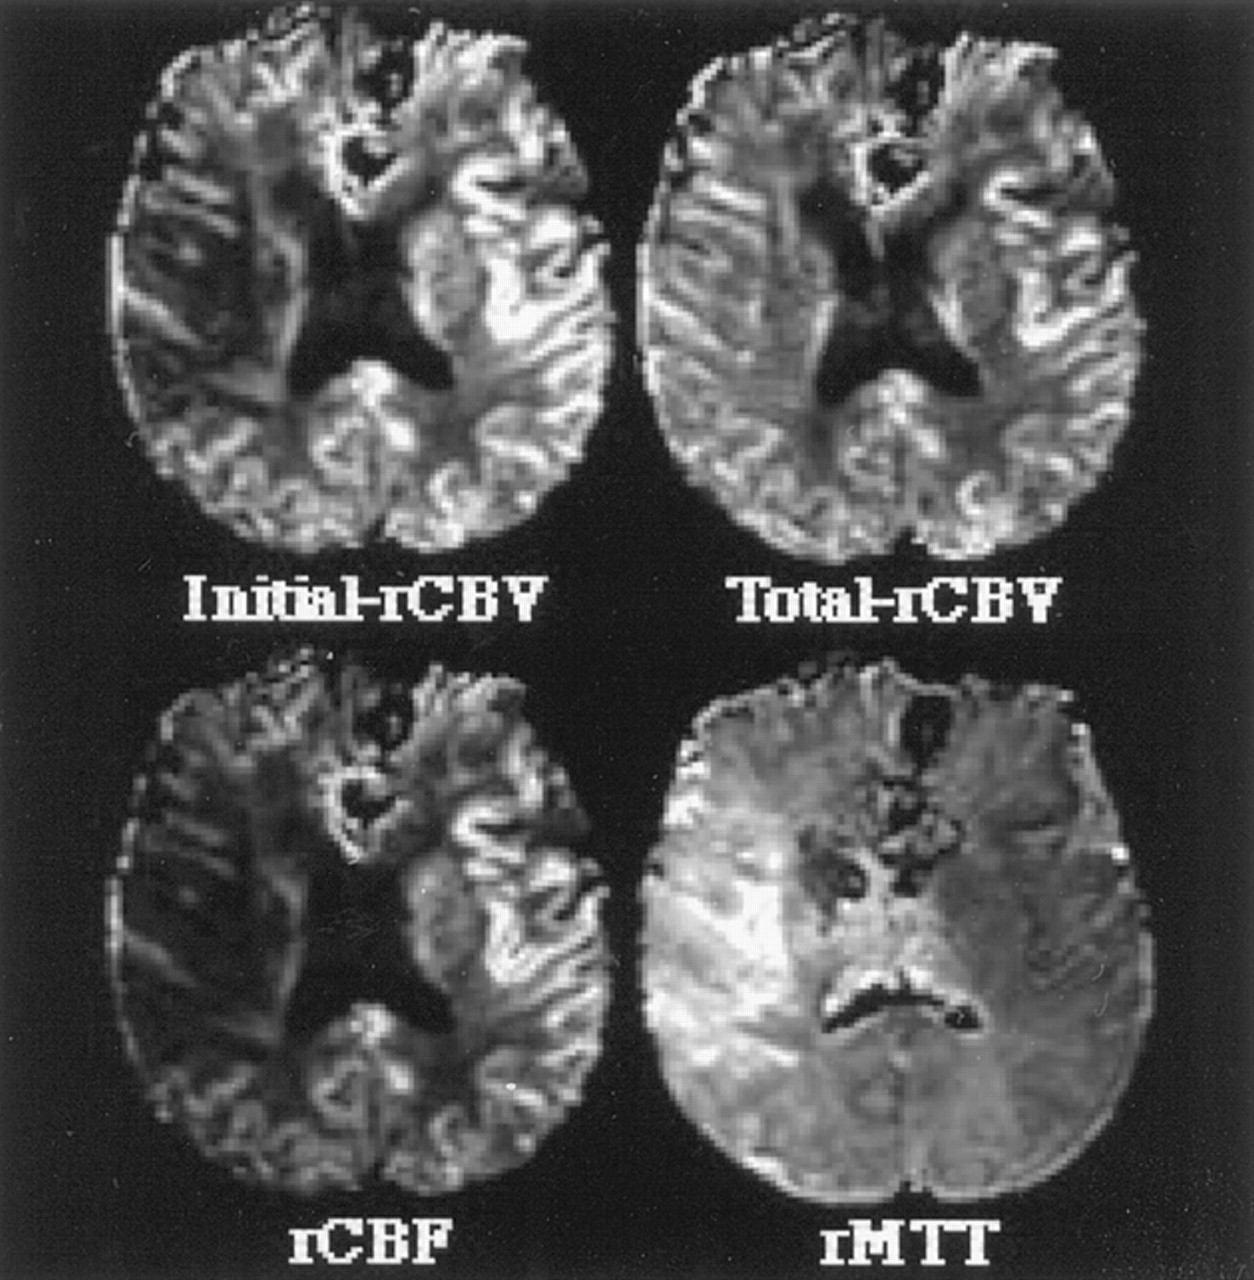

图2。这个图展示了水平切片两种不同脑血容量cb v()都未地图(cb v初始相对[rCBV],都未总rCBV),相对平均运输时间(rMTT)地图,和一个图像代表相对脑血流量(rCBF)。看到更多的细节关于这些图片的方法计算。

之间的各种估计rCBV,最初的操作半影rCBV是最好的预测。最初rCBV反映曲线下的面积曲线的初始部分,因此指数加权的rCBV流入血液的体积。最初rCBV非常类似于rCBF在这项研究中,这中可以看到图2而在表1显示类似的比例差异半影和缺血性核心定义的操作。虽然最初的rCBV显著降低,总rCBV显著增加的运营半影侧控制区域。然而,总rCBV不如最初rCBV差异化运营从缺血半影的核心。rCBV总数的增加在我们的操作半影同意大多数宠物cb v测量显示增加缺血半影中都未引起的早期代偿反应脑灌注压降低。12,13rCBF略优于初始rCBV在区分半影从核心定义的操作。rMTT显著延长操作半影,更在缺血性核心。然而,rMTT是不如其他标记区分从缺血半影核心定义的操作,但在区分异常(即是一个优秀的标志。,核心和半影)从正常灌注(见表1)。